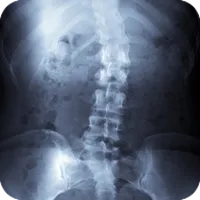

Scoliosis

scoliosis_chiropractic.png

Scoliosis is a sideways curve of the spine that causes stiffness and pain. People with scoliosis have a sideways curve in their spine that makes an "S" or "C" shape.

Scoliosis is derived from the Greek term meaning curvature. People with scoliosis have a sideways curve in their spine that makes an "S" or "C" shape. The vertebrae can rotate at the thoracic level of the spine causing this curve and resulting in a hump near the rib cage. If the curve is more than 60 degrees it is considered serious. Usually this curve makes the waist or shoulders uneven. And unlike the normal curvature of the spine, adjusting your posture will not correct the problem.